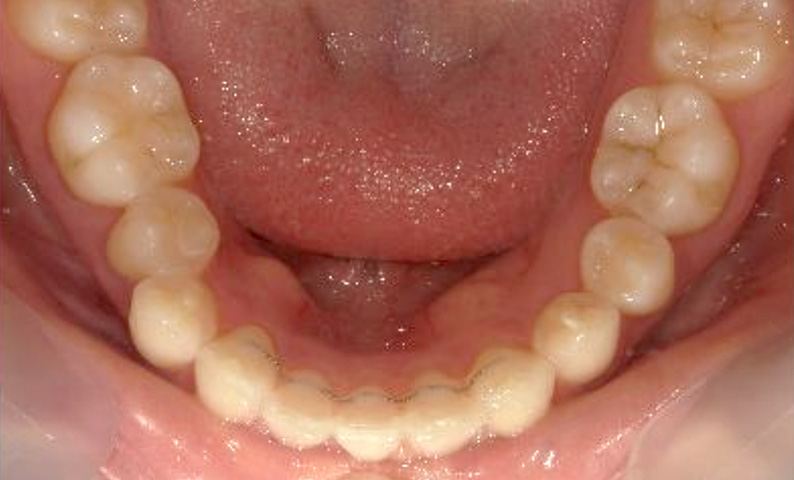

症例_001 下顎だけの部分矯正

治療期間:6ヶ月金額:27万円+税女性前歯のガタガタ下の前歯だけ

| Before | After |

|---|---|

|